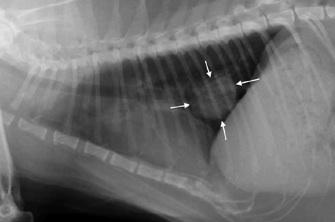

Parmi la cohorte, cinq personnes avaient des cellules cancéreuses circulantes détectées grâce au test, alors même que l’imagerie ne révélait aucune tumeur. Ces personnes ont été suivies régulièrement. Des très petites tumeurs (nodule) ont commencé à se former au bout de deux ans, en moyenne, après le test sanguin (entre 1 an et 4 ans selon les sujets). L’analyse de ces nodules a confirmé le diagnostic d’un cancer du poumon.